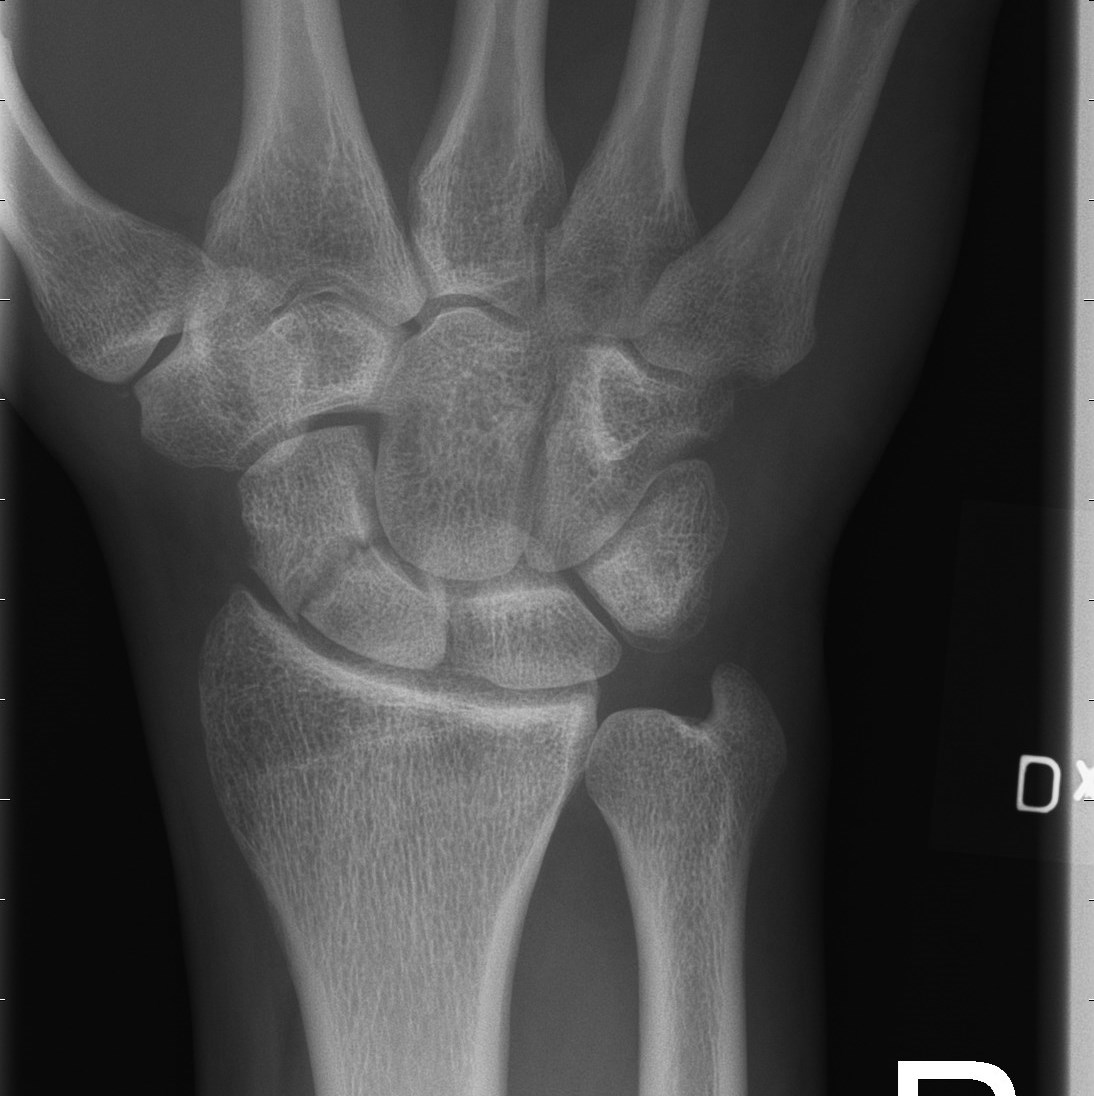

Scaphoideumfraktur

Symtom

Palpationsömhet i fossa Tabatiére, smärta vid axialt kompression av tummen samt vid dorsalextension respektive radialdeviation av handleden.

Drabbar ofta yngre individer i samband med sportutövning eller efter annat kraftigt dorsalextensionsvåld. Frakturen är ofta svår att identifiera på slätröntgen varför upprepade undersökningar och/eller CT/MR kan behövas.

Scaphoideum är dåligt vaskulariserad och ofta läker dessa frakturer (ffa proximala polfrakturer) långsamt; 3 månader i gips är normaltid! Gipsen skall immobilisera tumbas, handled och begränsa armens pro-supination. Utebliven läkning (pseudartros) är relativt vanligt och risken ökar om frakturen inte immobiliseras från skadetillfället.

Vid misstanke om scaphoideumfraktur (adekvat trauma, ömhet i fossa Tabatiére)

- Immobilisera i scaphoideumgips även om röntgen bedöms normal.

- Beställ då röntgenkontroll (utan gips) efter 10-14 dagar! Om röntgen är u a även efter 2 veckor, men status kvarstår: ordna snar MR- eller CT-undersökning!

Om skadan missas leder den mycket ofta till pseudartros och senare artros. En smärtsam pseudoartros kräver ofta att man tillför ben från crista illiaca vid operation och vid en handledsartros krävs någon typ av steloperation eller annat större ingrepp.

Det är tyvärr vanligt att frakturen missas då patienten kan uppleva symtomen som en distorsion, men det är också ganska vanligt att det missas av den undersökande doktorn. Detta sammantaget (s.k. 'patient's and doctors’ delay') innebär tyvärr att pseudoartrosoperationer är ganska vanliga.